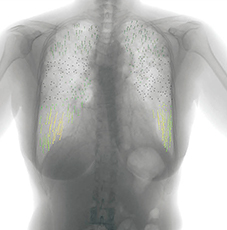

図3 症例1:変位のベクトル表示画像

胸部単純X線写真では,下肺野優位に網状影,すりガラス状陰影が認められる。単純CT画像(図1)では,上肺野ほどの陰影はないが,下肺野には気管支血管側周囲から胸膜下にかけて網状影,すりガラス状陰影が認められ,膠原病肺が疑われる。胸部X線動態画像(図2)では,正常例と比べて下肺野および胸郭の幅の動きが悪い印象であった。また,胸部X線動態画像の呼気時から吸気時にかけての変位をベクトル表示した画像(図3)を見ると,当院の正常コントロール例と比較して下肺野の動きが悪い印象である。

さらに,IPにおける動きの特徴として,下肺野優位の症例では下肺野の動きおよび胸郭の動きが悪く,上肺野優位の症例では全体的に動きが悪いという印象がある。また,いずれの症例も胸郭の動きは上部の方が下部に比べて良好な傾向が見られた。これらについては,まだ定量的な解析を行っていないが,IPのサブタイプによる動きの違いについても,今後検討していきたい。